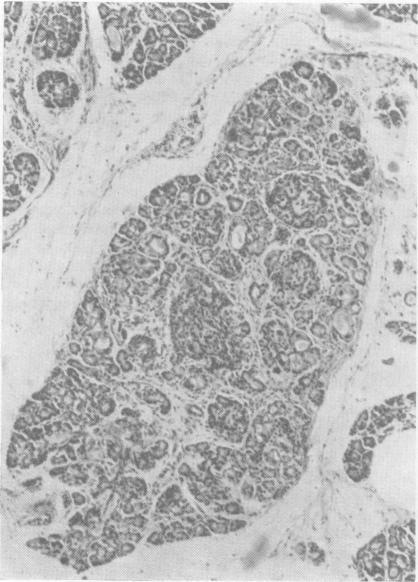

Inclusion disease in childhood.

Arch Dis Child. 1951 Dec;26(130):588-600. doi: 10.1136/adc.26.130.588.